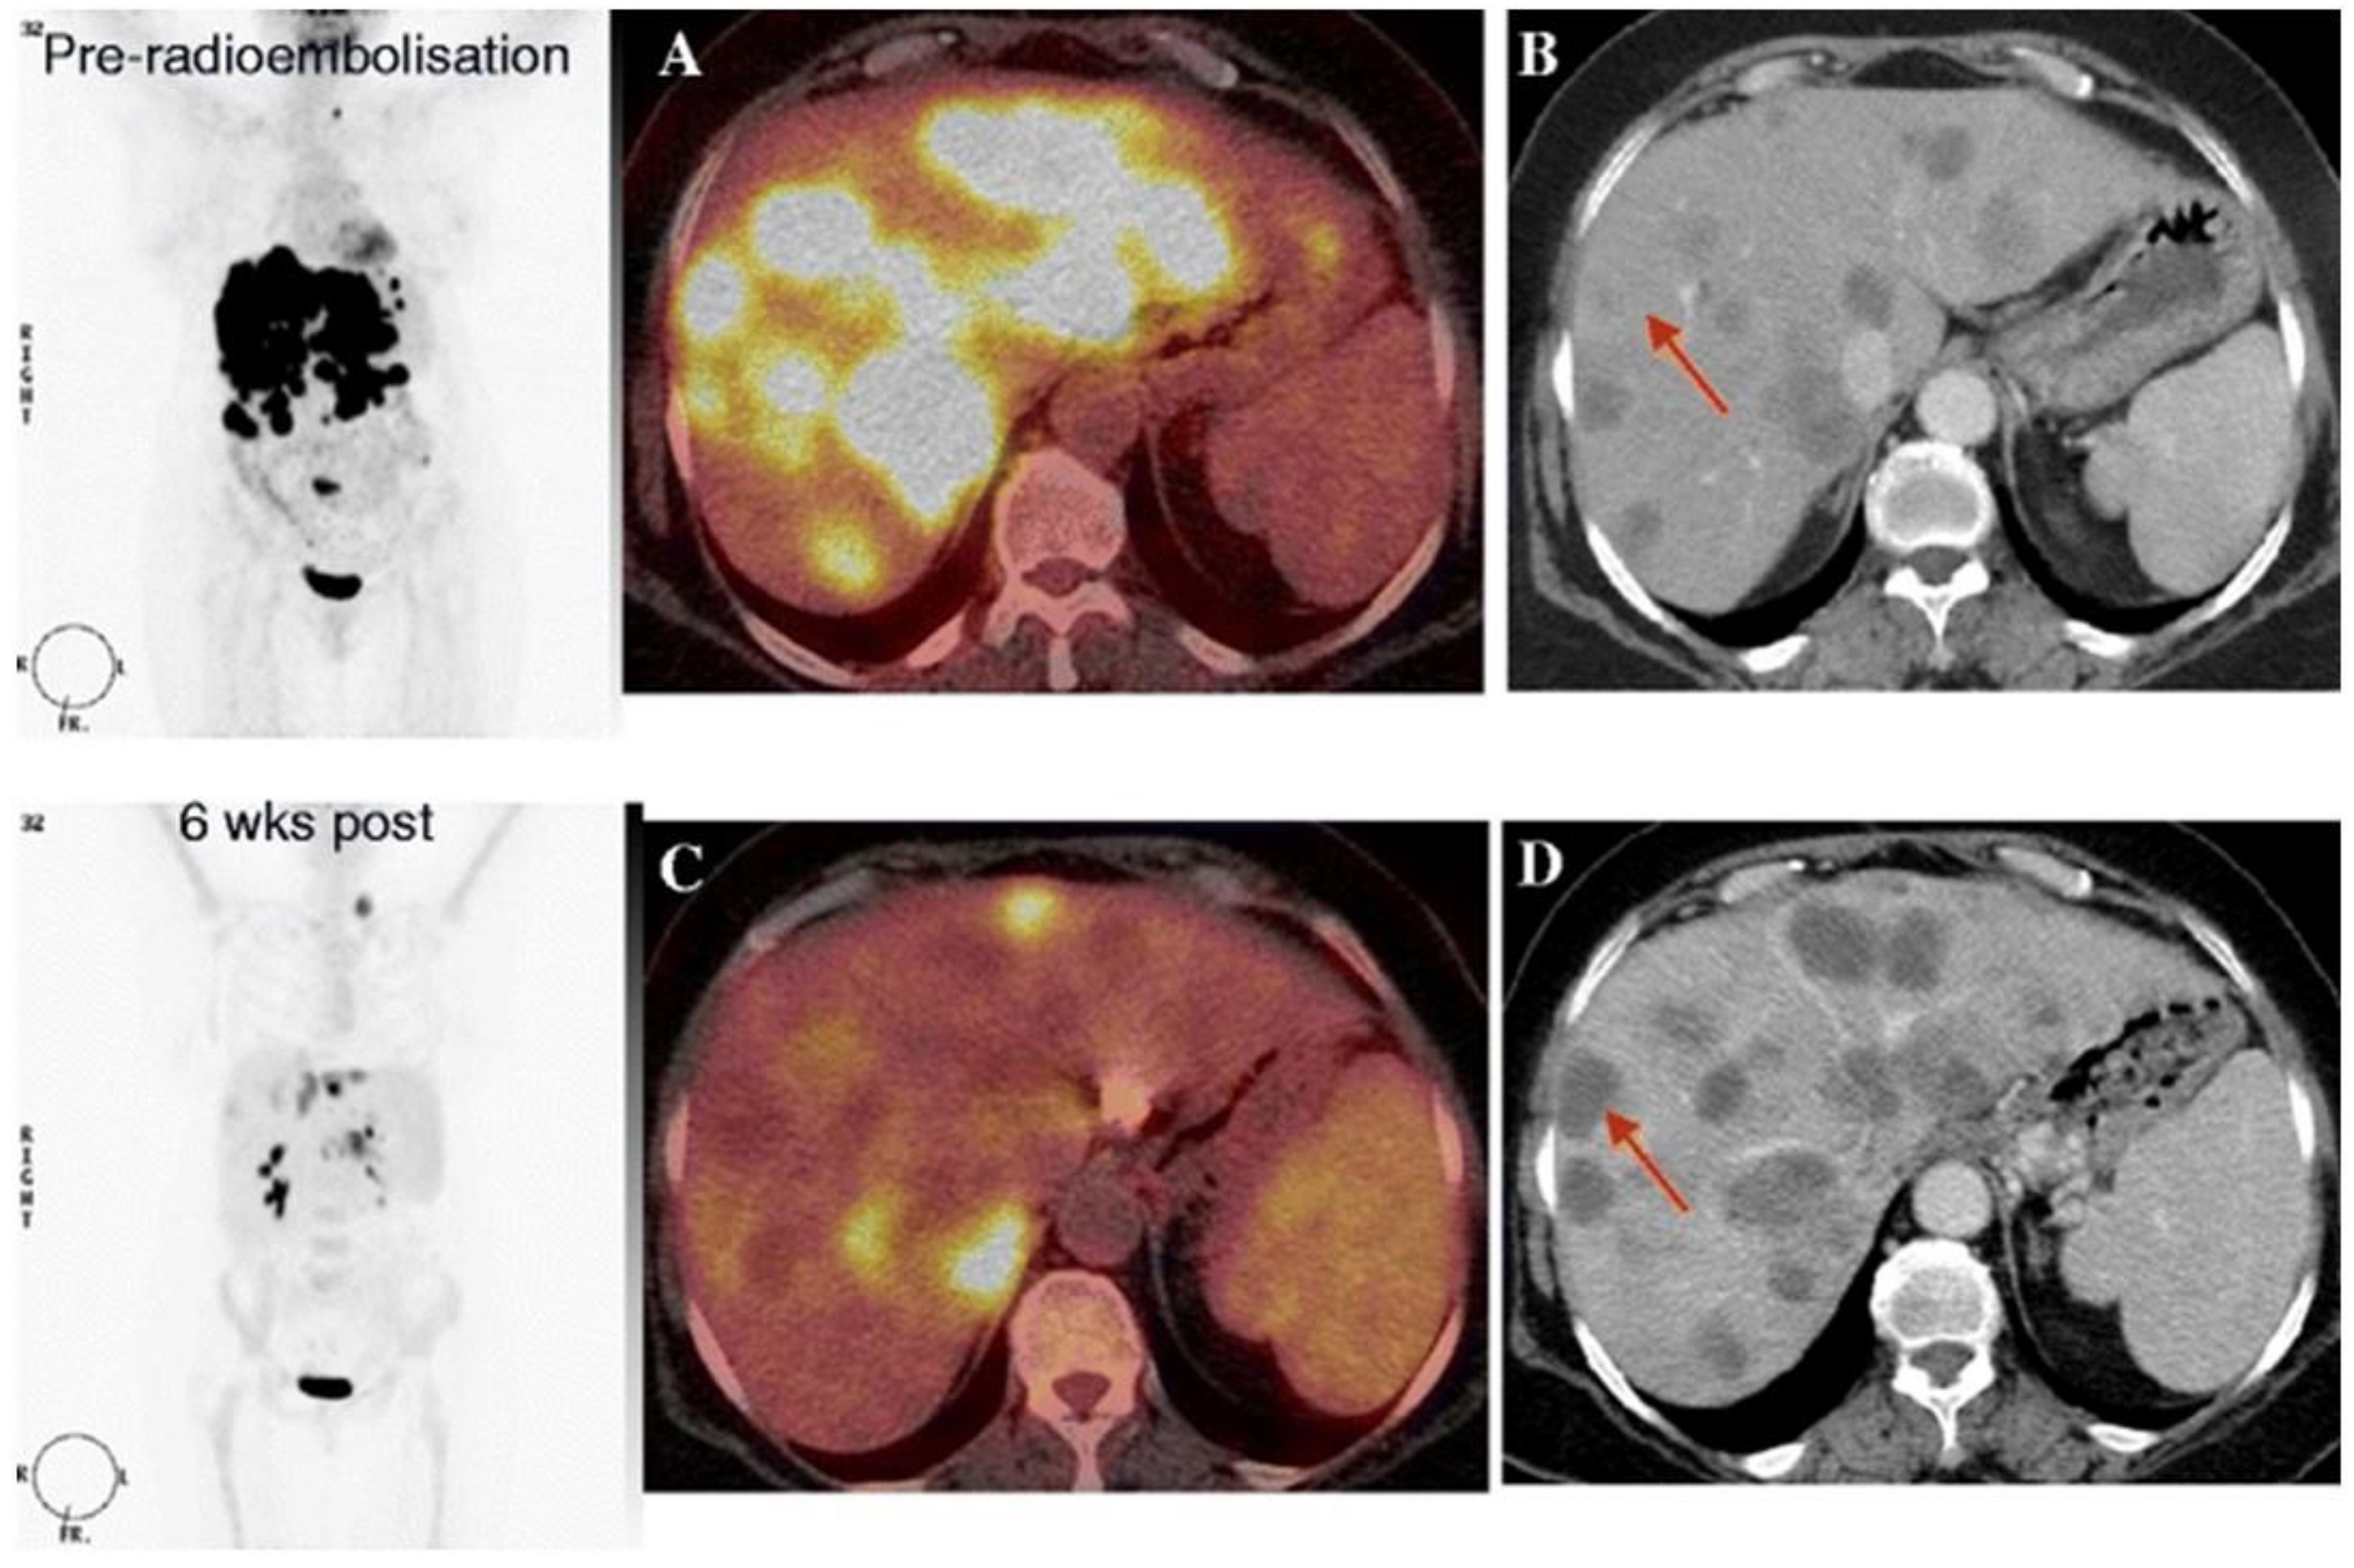

Summary

Multiple parameters such as SUVmax, MTV, and TLG seem to have a predictive value on patient outcomes and could be used as a prognostic marker for the prediction of long-term outcomes in CRLM treated by radioembolization. The additional value of 18F-FDG-PET-CT imaging compared with ceCT imaging is shown in Figure 4, and an overview of included studies and results is summarized in Table 5.

Figure 4.

18F-FDG PET-CT images before and 6 weeks after radioembolization. Coronal PET-only images (left panel), fused 18F-FDG PET-CT images (A,C), and contrast-enhanced CT images (B,D). Pretreatment 18F-FDG PET-CT and contrast-enhanced CT images show multiple hepatic lesions (A,B). Posttreatment 18F-FDG PET-CT imaging shows a partial metabolic response (C), whereas contrast-enhanced CT imaging suggests progressive disease. Adapted from: The role of early 18F-FDG PET/CT in prediction of progression-free survival after 90Y radioembolization: comparison with RECIST and tumour density criteria. I. Zerizer et al. Eur J Nucl Med Mol Imaging. 2012 Sep;39(9):1391-9. doi: 10.1007/s00259-012-2149-1. Epub 2012 May 30.